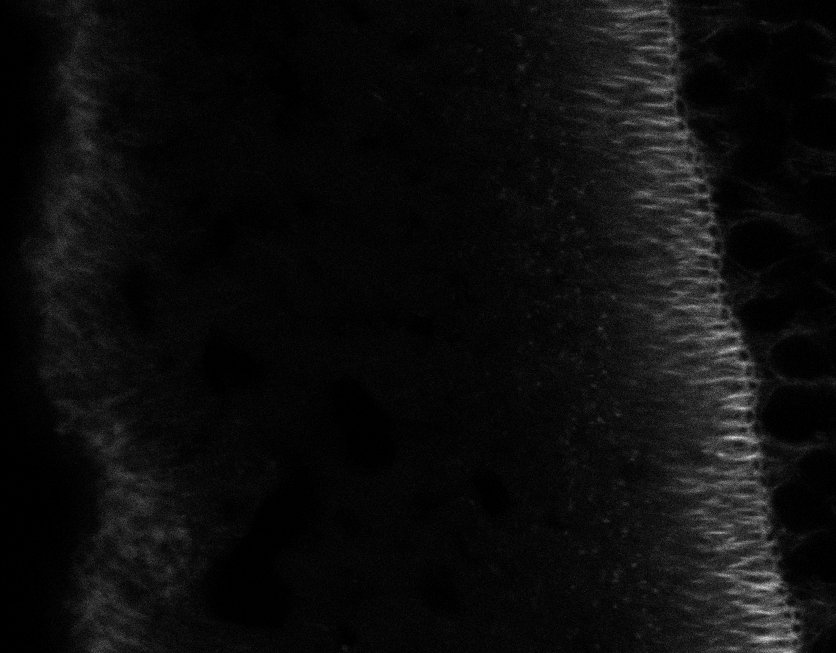

Tubulin

Tubulin - Bip

Tubulin - Nuc